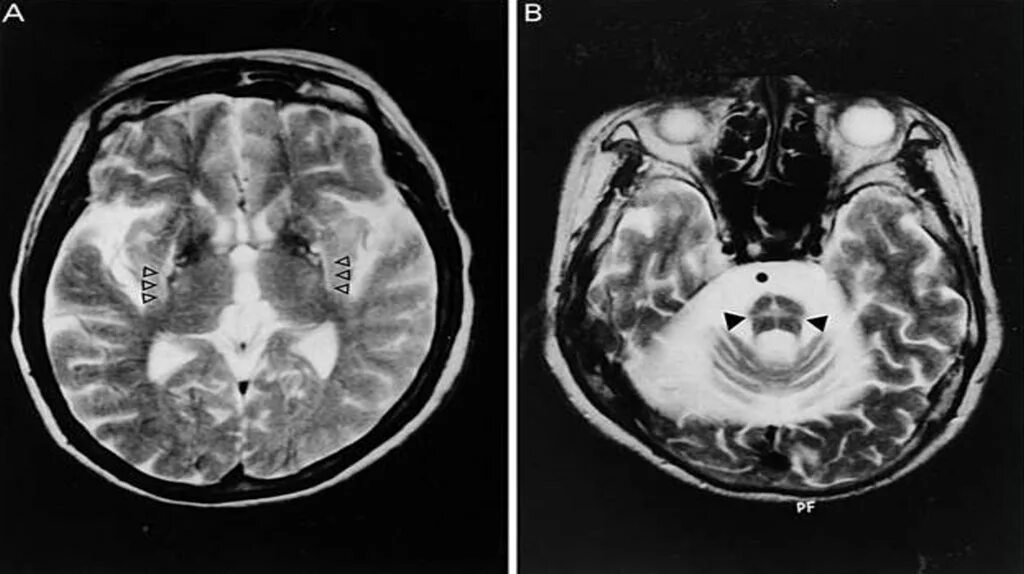

Диффузная церебральная атрофия степени